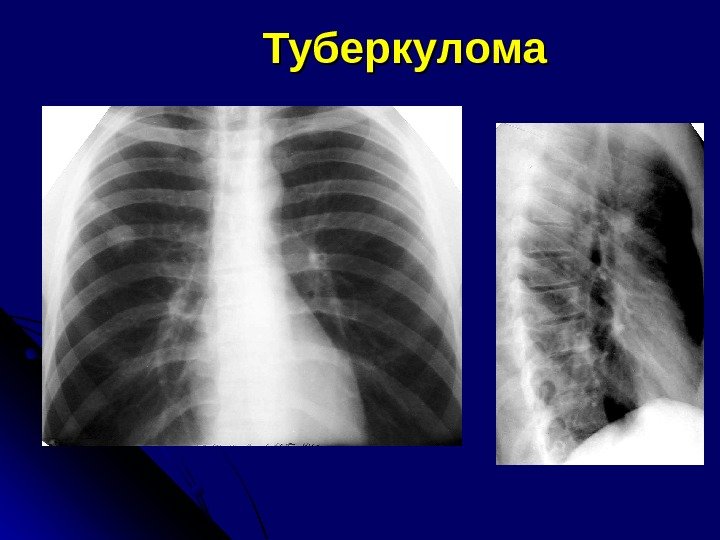

ТУБЕРКУЛОМЫ округлые единичные (более 1 см в диаметре) или множественные фокусы туберкулезного воспаления с казеозом и фиброзной капсулой Частота Одиночные туберкуломы — 80 -85% Мн ожественные – в 15 -20%

Р и КТ-признаки туберкулом Округлое образование Верхняя доля (чаще), S 6 Кортикальный отдел Контуры – четкие, ровные, волнистые Не соприкасается с плеврой Фон – мелкие очаги, участки эмфиземы, отдельные тяжи к плевре Стенки бронхов незначительно утолщены

КТ-признаки туберкулом Отличительный признак – наличие очаговых, слоистых, диффузных обызвествлений (денсит. плотность > 200 HU)HU) Отличительный признак – при динамической КТ – чаще денсит. показатели не меняются, иногда накопление КВ по капсуле – эффект краевого усиления

Туберкулома